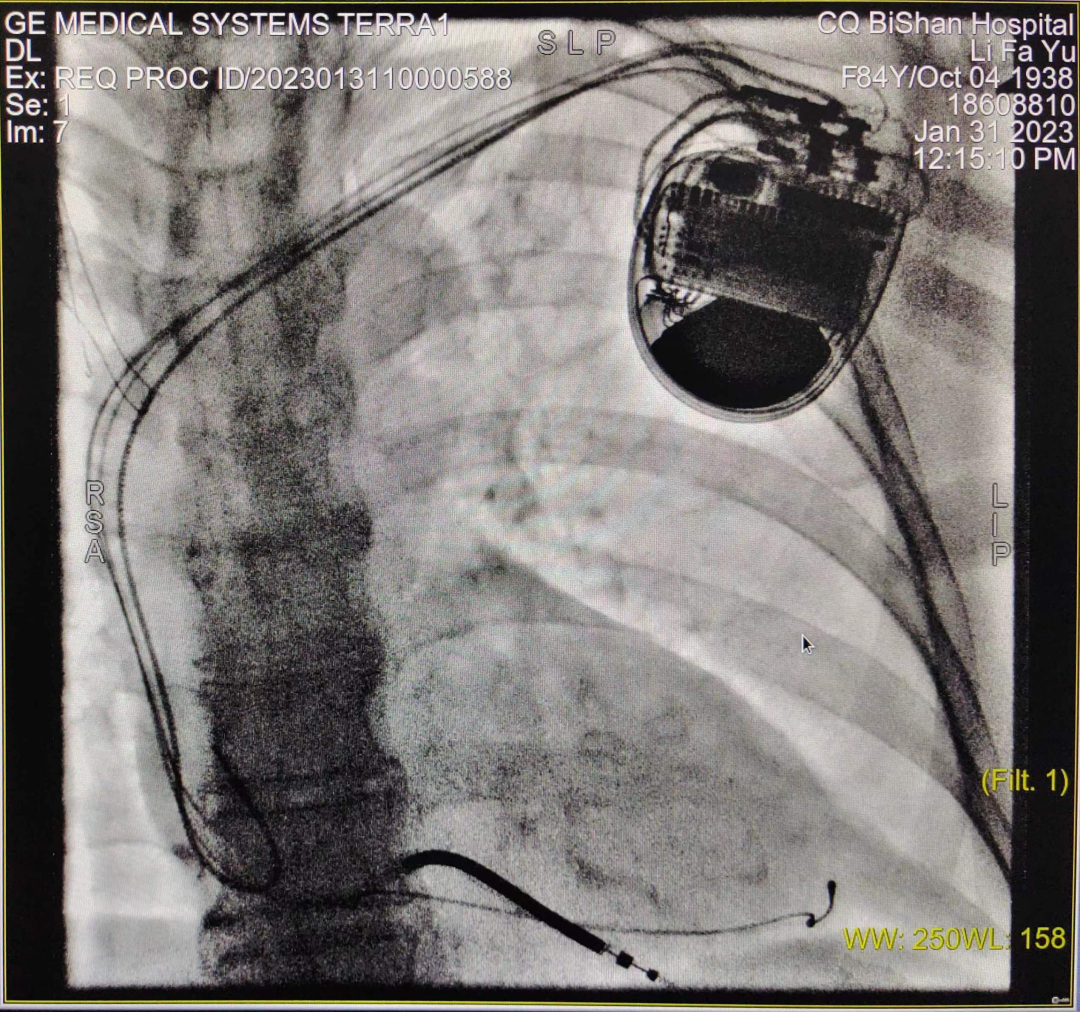

CRT-D植入術(shù)進(jìn)行中

于長青主任高度重視,結(jié)合患者既往病史、治療史,先后多次組織科室團(tuán)隊(duì)及醫(yī)院MDT團(tuán)隊(duì)討論,并報(bào)請醫(yī)務(wù)科批示,最終決定給該患者安置三腔起搏器,實(shí)施雙心室同步起搏的心臟再同步化治療,改善患者的心力衰竭癥狀。科室起搏電生理團(tuán)隊(duì)經(jīng)過充分的術(shù)前準(zhǔn)備,于1月31日成功為患者實(shí)施CRT-D介入手術(shù),手術(shù)過程順利,患者無任何不適,術(shù)后5天即安全出院。術(shù)后心電圖提示:竇性心律,雙心室起搏心律,QRS寬度120-130ms,患者勞累氣促癥狀較前明顯改善。